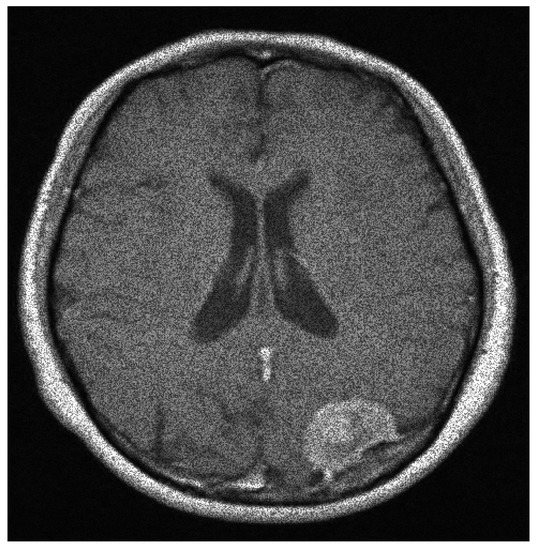

Figure 4.

The original speckle noisy image (example 1) with .